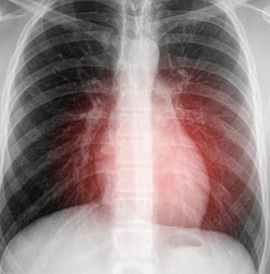

In a last-ditch effort to save a dying man’s life, doctors turned to booze—and it worked. A 77-year-old British man named Ronald Aldom is doing “fantastically well” since his unusual heart rhythm was treated successfully with pure ethanol (the same substance found in alcoholic drinks). When other treatments had failed the ailing patient, his physician Dr. Tom Johnson stuck a catheter into a blood vessel located in the groin, and began pumping the pure ethanol towards the heart. This caused a controlled heart attack which destroyed the other tissue that was responsible for the irregular heartbeat. “He wasn’t going to leave hospital unless something was done,” says Johnson. “There was no other option.” It was the doctor’s first time using this method to treat Ventricular tachychardia (VT), which starts in the lower ventricles and can be fatal if left untreated. The rare procedure, which is generally used only as a last resort, is not routine in the US since the effects of the ethanol shot can be difficult to manage. “This is something you have to do electively,” says Dr. Richard Page, chairman of the department of medicine at the University of Wisconsin School of Medicine and Public Health. “This is not something you do on the fly in the middle of a cardiac arrest.” Regardless of the risks, Aldom is grateful to be recovering, and credits the unorthodox treatment with saving his life. “I think it’s wonderful that the doctors tried everything to help me,” he says. “If they hadn’t had done this I wouldn’t be here now.”